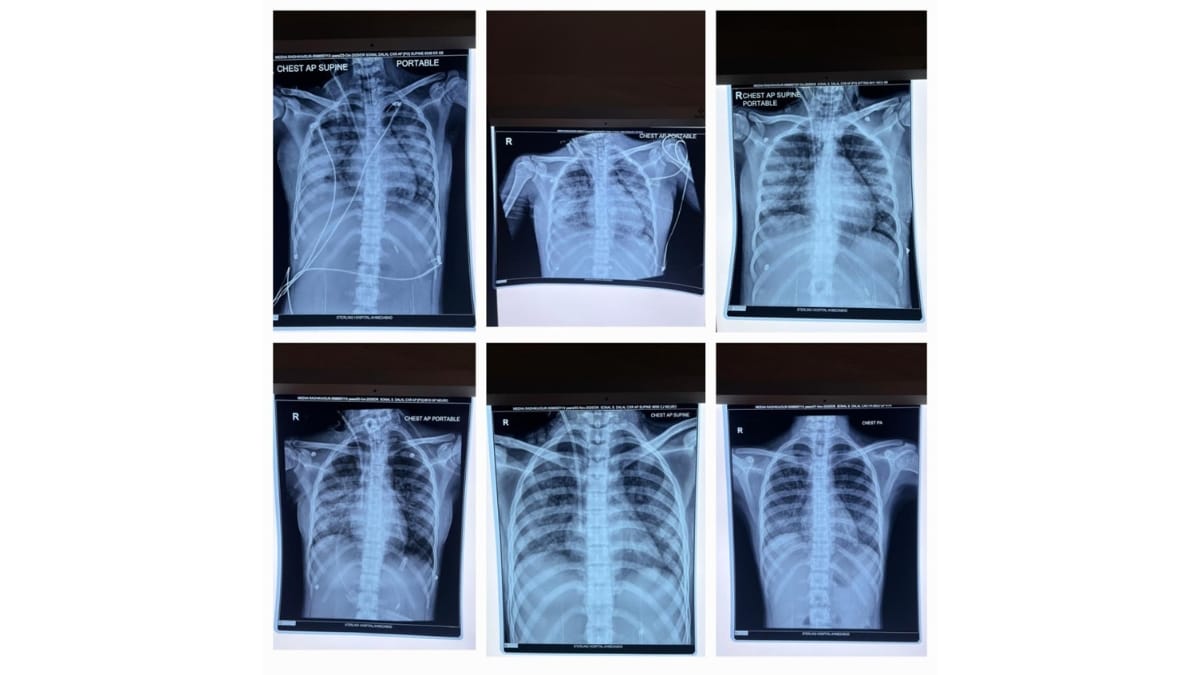

Sterling Hospital, Ahmedabad’s Dr Amrish Patel (Pulmonologist & Critical Care Specialist) explained that when the patient arrived, her oxygen levels were dangerously low, and she was struggling to breathe. She had been shifted from Rajasthan on ventilator support due to her fragile condition. The team immediately initiated specialised treatment to stabilise her. She was diagnosed with falciparum malaria, which had led to kidney damage, lung complications, and multi-organ involvement. After dialysis and medical management, she remained on ventilator support for 12 days, during which her life was saved through advanced care administered by the critical care team.

Dr. Amrish Patel (Pulmonologist & Critical Care Specialist) added that a bronchoscopy was performed to clear the secretions from her lungs. An essential step that further contributed to her recovery. As her condition improved, the ventilator support was gradually removed, and she was shifted to a normal room. By then, she had entered the recovery phase. After approximately 18 days of treatment, her life was saved through advanced care, and she was discharged in a stable and healthy condition.